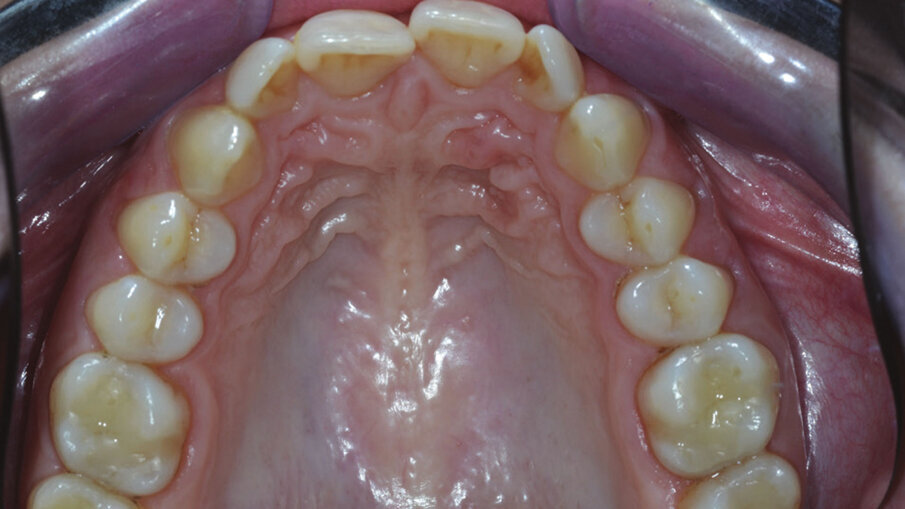

Figg. 4g, 4h_Foto occlusali di inizio trattamento.

Figg. 4g, 4h_Foto occlusali di inizio trattamento.

L’esame intraorale (Figg. 4a-4h) mostra un affollamento moderato in arcata superiore e inferiore e un morso profondo con un overbite di 5,29 mm, un rapporto inter-arcata di Classe II Suddivisione che si esprime con una Classe II testa a testa, sia molare sia canina a sinistra e una lieve Classe II canina e molare a destra. A complicare il quadro clinico le linee mediane non sono coincidenti, la superiore risulta deviata leggermente a destra. L’esame ortopantomografico mostra pregresse cure dentarie senza nessuna anomalia da segnalare. I valori cefalometrici dimostrano una tipologia brachifacciale con una sinfisi molto svirgolata, il che contrasta con un’eccessiva proclinazione anteriore degli incisivi.